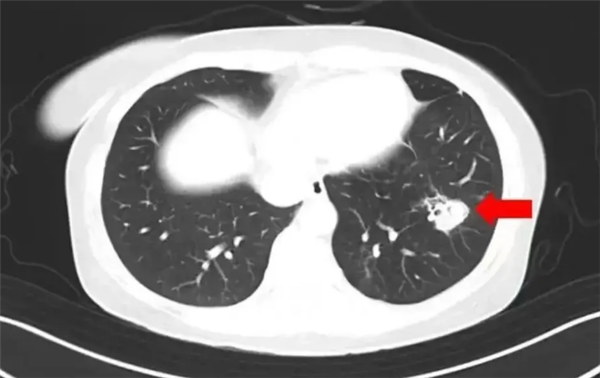

电脑知识网5月3日消息,据报道,近日,杭州萧山的沈女士因整理发霉衣柜不幸感染曲霉菌,引发高烧40℃住院治疗。经萧山区第一人民医院检查确诊为肺曲霉病,经过抗真菌治疗后已康复出院。

沈女士在换季整理衣柜时发现霉斑,未做防护就进行了彻底清理。随后出现持续高热、咳嗽等症状,就医检查发现气道壁布满白色菌斑,确诊为曲霉菌感染。据医生介绍,曲霉菌被世卫组织列为一类致癌物,其毒性是砒霜的68倍。

人体免疫系统受到攻击或免疫力较弱时,曲霉菌就可能进入肺部,引起肺曲霉病。